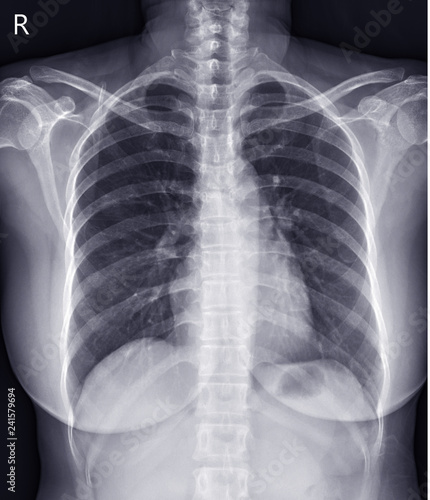

Рентген грудной клетки: Понимание и диагностика